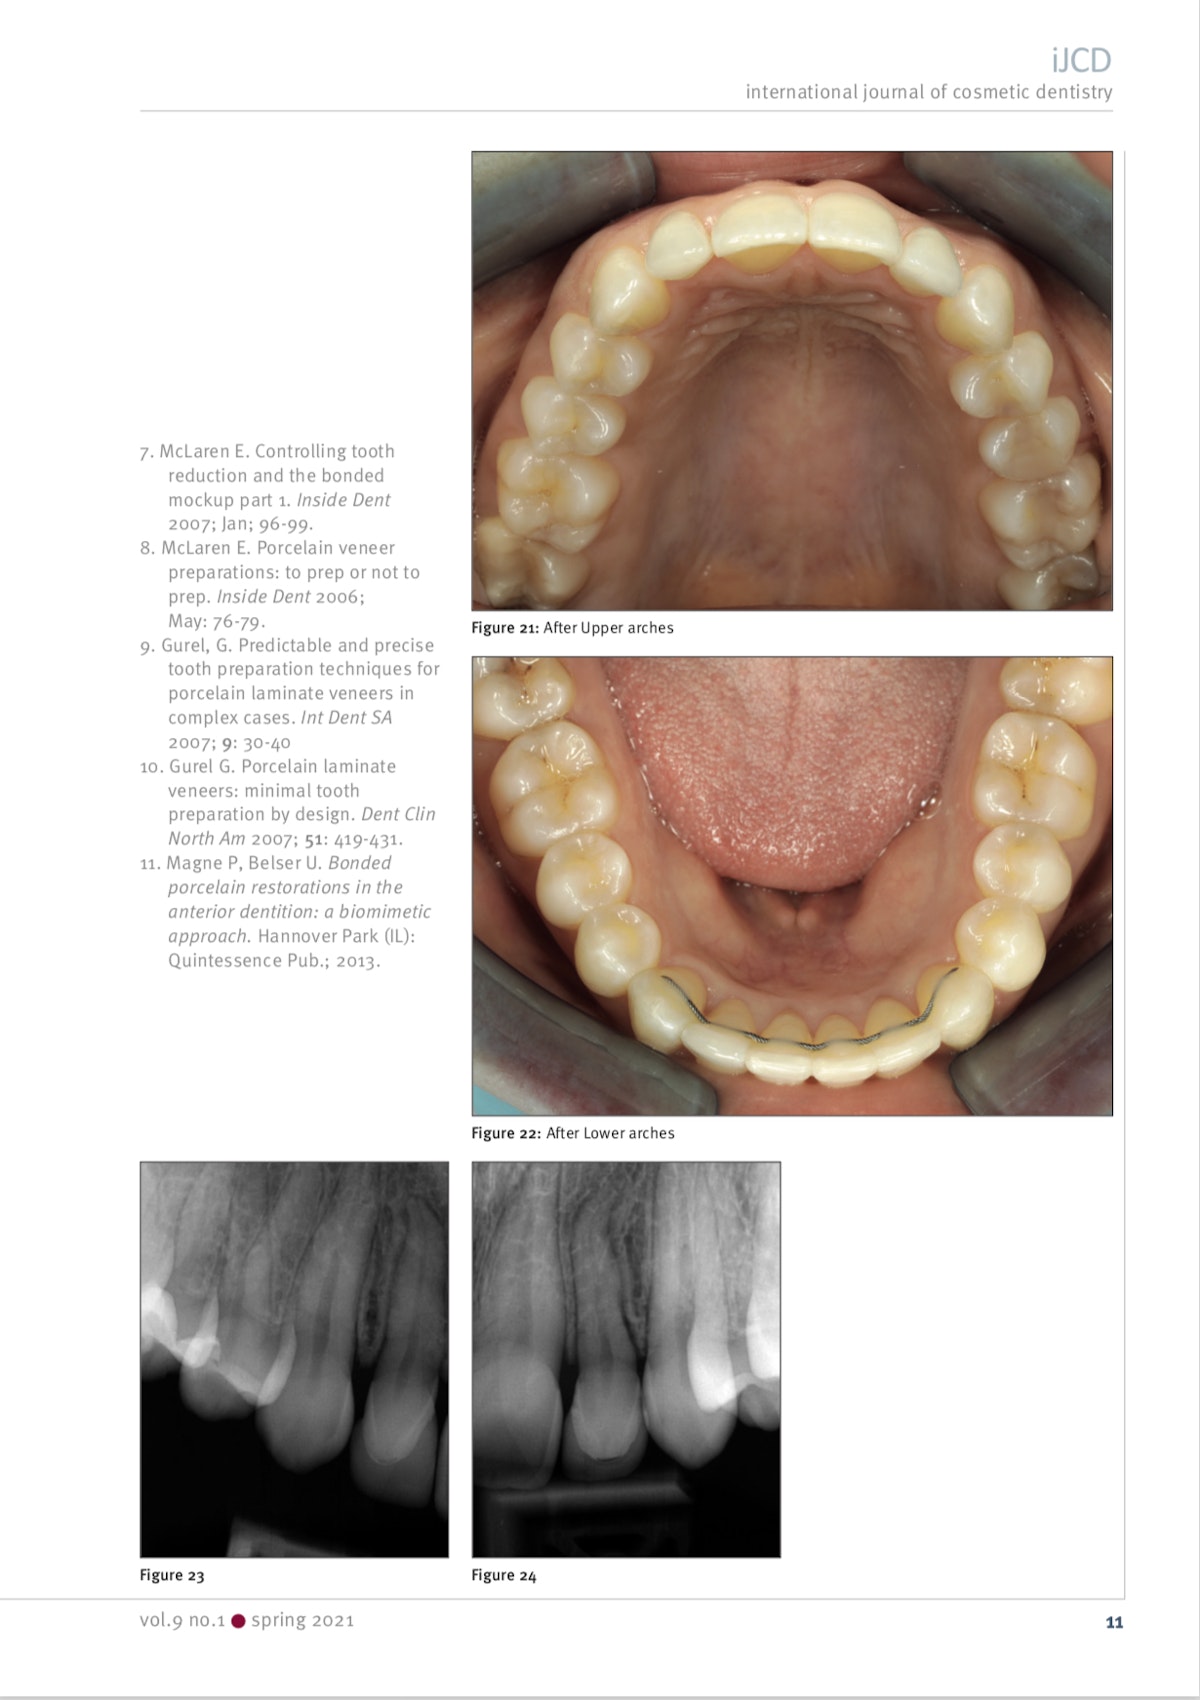

Ja syy sille miksi oikomista Invisalign -kalvoilla käytetään usein ennen laminaattihoitoja. Alla oleva hoito olisi ollut ehkä toteutettavissa ilman oikomistakin, mutta hampaita olisi silloin pitänyt hioa kohtuuttoman paljon. Oikomisella purentaa on parannettu, saatu purentavoimat jakautumaan hampaistossa oikein ja tätä kautta lopputuloksesta mahdollisimman pitkäkestoinen.

1. Alkutilanne ennen oikomista

2. 6kk Invisalign -hoidon jälkeen

3. Hampaat hiottuna kuoria varten

4. Keraamiset hammaslaminaatit kymmenessä ylähampaassa

Journal of Cosmetic Dentistry 2019 volume 35 issue 3

International Journal of Cosmetic Dentistry vol. 9 no. 1 spring 2021